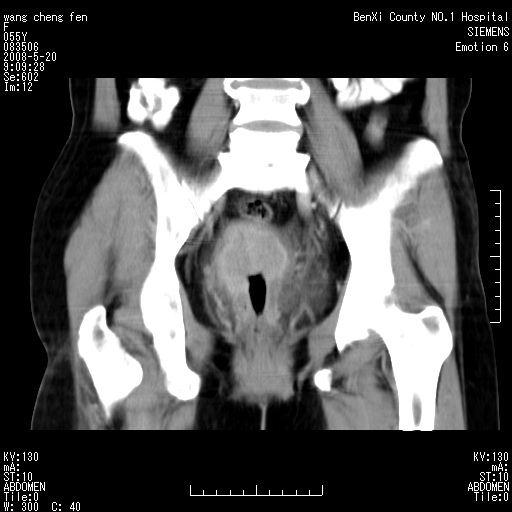

女、绝经后阴道流血3个月

左侧附件区巨大囊实性病灶,边缘光整,病灶囊壁较厚,增强示囊壁及实性部分明显强化,强化呈度与宫体实质大致相同,宫腔积液征像,未见盆腔积液等其他异常,考虑左侧卵巢囊腺癌,不除外囊腺瘤及浆膜下肌瘤坏死

支持浆膜下子宫肌瘤.之前由于网络原因未看全图片,现在重看,宫颈见一类圆形低密度影,增强轻度强化,低于肌层强化,宫腔扩大,考虑宫颈癌伴宫腔积液可能性大.

囊实性肿块分隔厚度较大,厚薄不均,增强实性成分明显强化,有不规则阴道流血,卵巢囊腺癌可能性大。

1,宫颈部占位,宫颈癌?2,左侧附件区囊实性占位,界较清,实质部分强化明显。考虑浆膜下或阔韧带肌瘤囊变可能大。囊腺类肿瘤不除外。